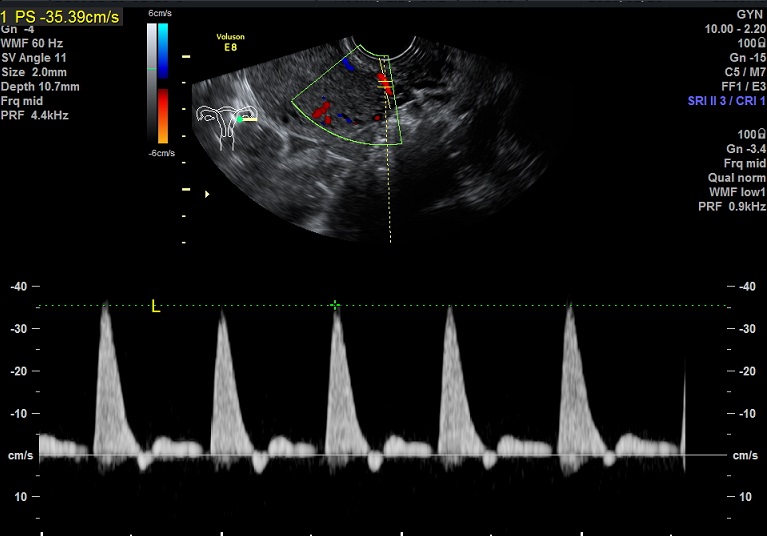

2015-3-19 月经第24天检查 内膜厚0.6cm 内膜血流:1级 内膜波动不明显 左卵巢黄体 子宫动脉: L:PSV:27.3cm/s EDV:4.7cm/s RI:0.83 S/D:5.8 PI:2.5 R: PSV:28.8cm/s EDV:2.0cm/s RI:0.93 S/D:14.4 PI:3.8 舒张早期血流缺失 检验: 2015-3-11 E2: 155.42 LH: 7.00 FSH: 4.43 P: 2.45 |

2015-3-19图示